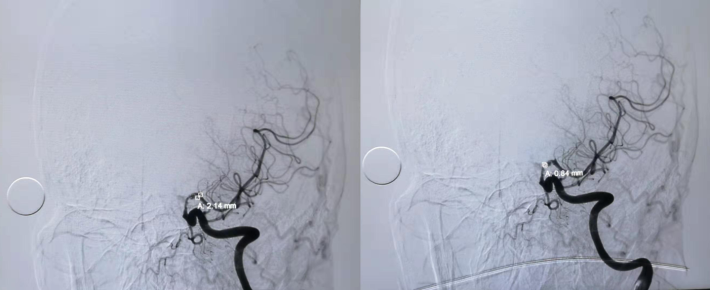

微导丝通过狭窄血管段

放置微导丝远端至左侧大脑中动脉上干M2段

3mm*15mm球囊扩张

球囊扩张后